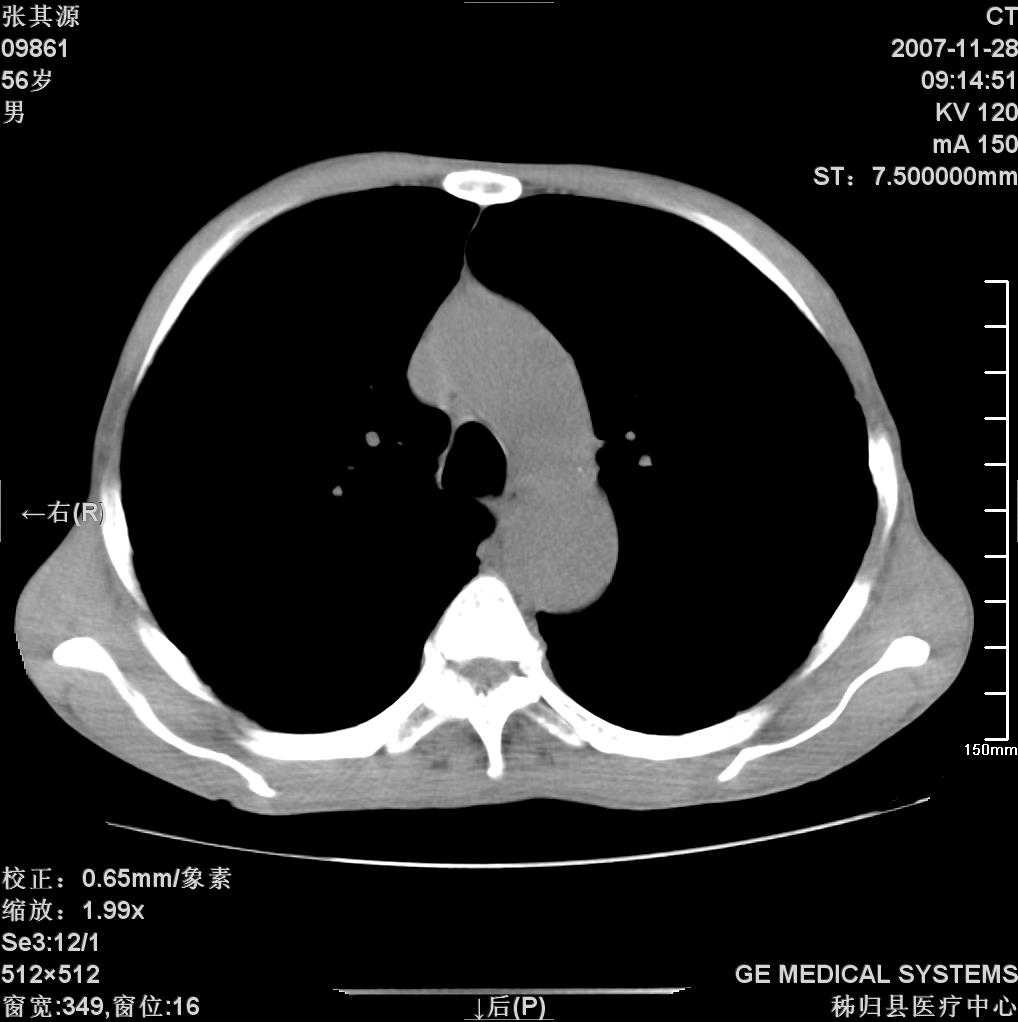

患者因阻塞性黄疸入院,发病前10天持续中等程度发烧.术前检查发现两肺弥漫性病变,请各位大虾会诊,除了考虑急性血源性肺结核外,还有其他什么疾病可能.

补充一下,该患者没有与尘肺相关职业史。请大家帮忙会诊一下,外科医生打算为其做胆总管肿瘤做手术的,现在在等我们的结果。谢谢各位了。

双肺多发粟粒样病灶,右肺胸膜下结节样病灶,气管前腔静脉后及隆突下均见肿大淋巴结,结合胆道肿瘤病史首先考虑转移。另外心影密度略低,时间格显示,是否有贫血?查明白再手术吧!